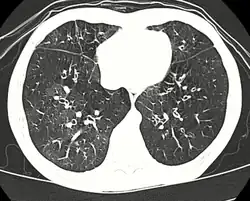

Early in the disease chest radiography is typically normal but may show hyperinflation.[6] As the disease progresses a reticular pattern with thickening of airway walls may be present.[4][6] HRCT can also show air trapping when the person being scanned breathes out completely; it can also show thickening in the airway and haziness in the lungs.[11] A common finding on HRCT is patchy areas of decreased lung density, signifying reduced vascular caliber and air trapping. This pattern is often described as a "mosaic pattern", and may indicate bronchiolitis obliterans.[6]